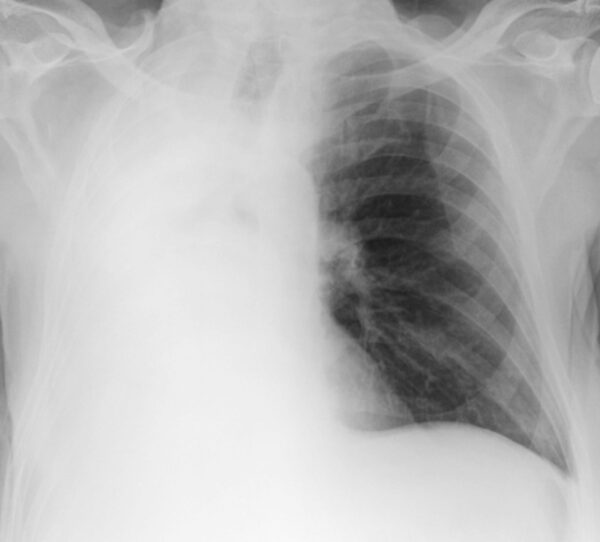

https://radiopaedia.org/cases/hemithorax-white-out-lung-collapse